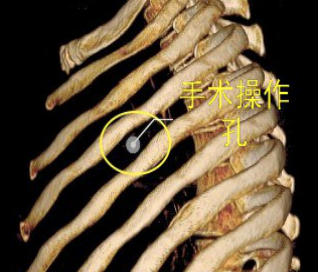

當(dāng)前,絕大多數(shù)的肺大泡手術(shù)均可在電視胸腔鏡(VATS)下完成,2/3的患者術(shù)后癥狀明顯改善。與家長溝通后,鄧意平成功為小王開展單孔胸腔鏡下左側(cè)肺大泡切除術(shù)。

較兩孔、多孔胸腔鏡手術(shù)或傳統(tǒng)手術(shù),單孔手術(shù)具有創(chuàng)傷更小、出血更少、術(shù)后疼痛更輕、瘢痕小、切口更加美觀、術(shù)后恢復(fù)快、住院時(shí)間短等優(yōu)勢(shì)。但手術(shù)中所有器械(包括觀察鏡、吸引器、電凝鉤、切割閉合器、雙關(guān)節(jié)等各種操作器械)都要是從一個(gè)小“孔”進(jìn)入,器械之間的互相干擾,同時(shí)器械與觀察鏡幾乎平行,視野非常狹窄,手術(shù)難度明顯,增加極其考驗(yàn)醫(yī)生的技術(shù)。